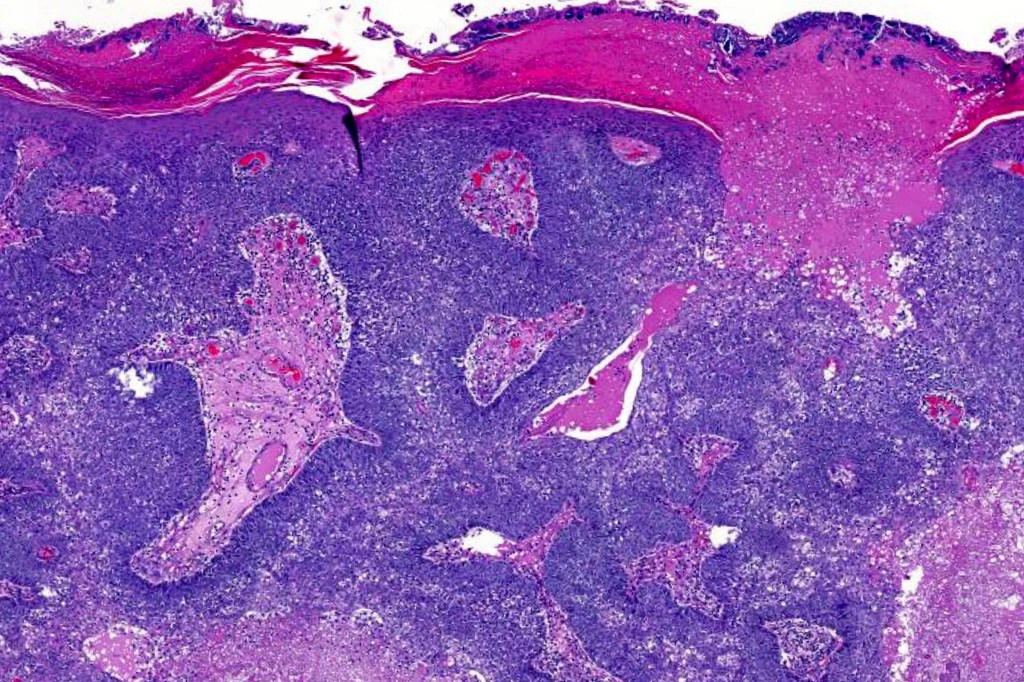

•Well differentiated lobular growth pattern though to a poorly differentiated tumor often showing a diffuse, infiltrating border which may extend into the subcutaneous fat

•May be associated with Pagetoid spread

•Tumors are composed of an admixture of darkly staining basaloid cells with hyperchromatic or vesicular nuclei and more obvious sebaceous cells with eosinophilic, bubbly, multivacuolated cytoplasm frequently indenting the nucleus (scalloped)

Sebaceous carcinoma from a patient with Muir-Torre syndrome kindly shared by Dr. Antonina Kalmykova.